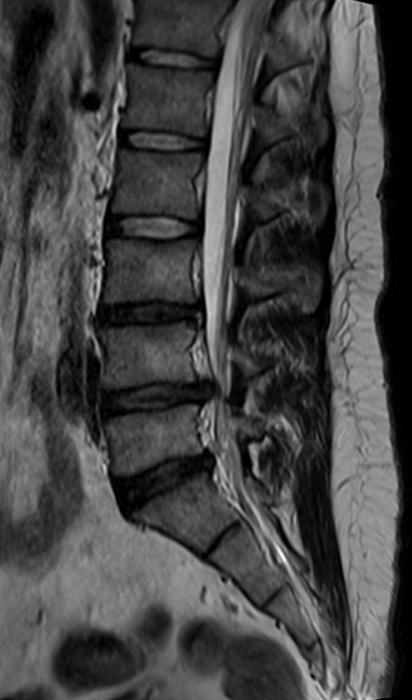

МРТ пояснично-крестцового отдела позвоночника

Магнитно-резонансная томография пояснично-крестцового отдела позвоночника – важный метод исследования, который позволяет оценить состояние пояснично-крестцового отдела позвоночника.